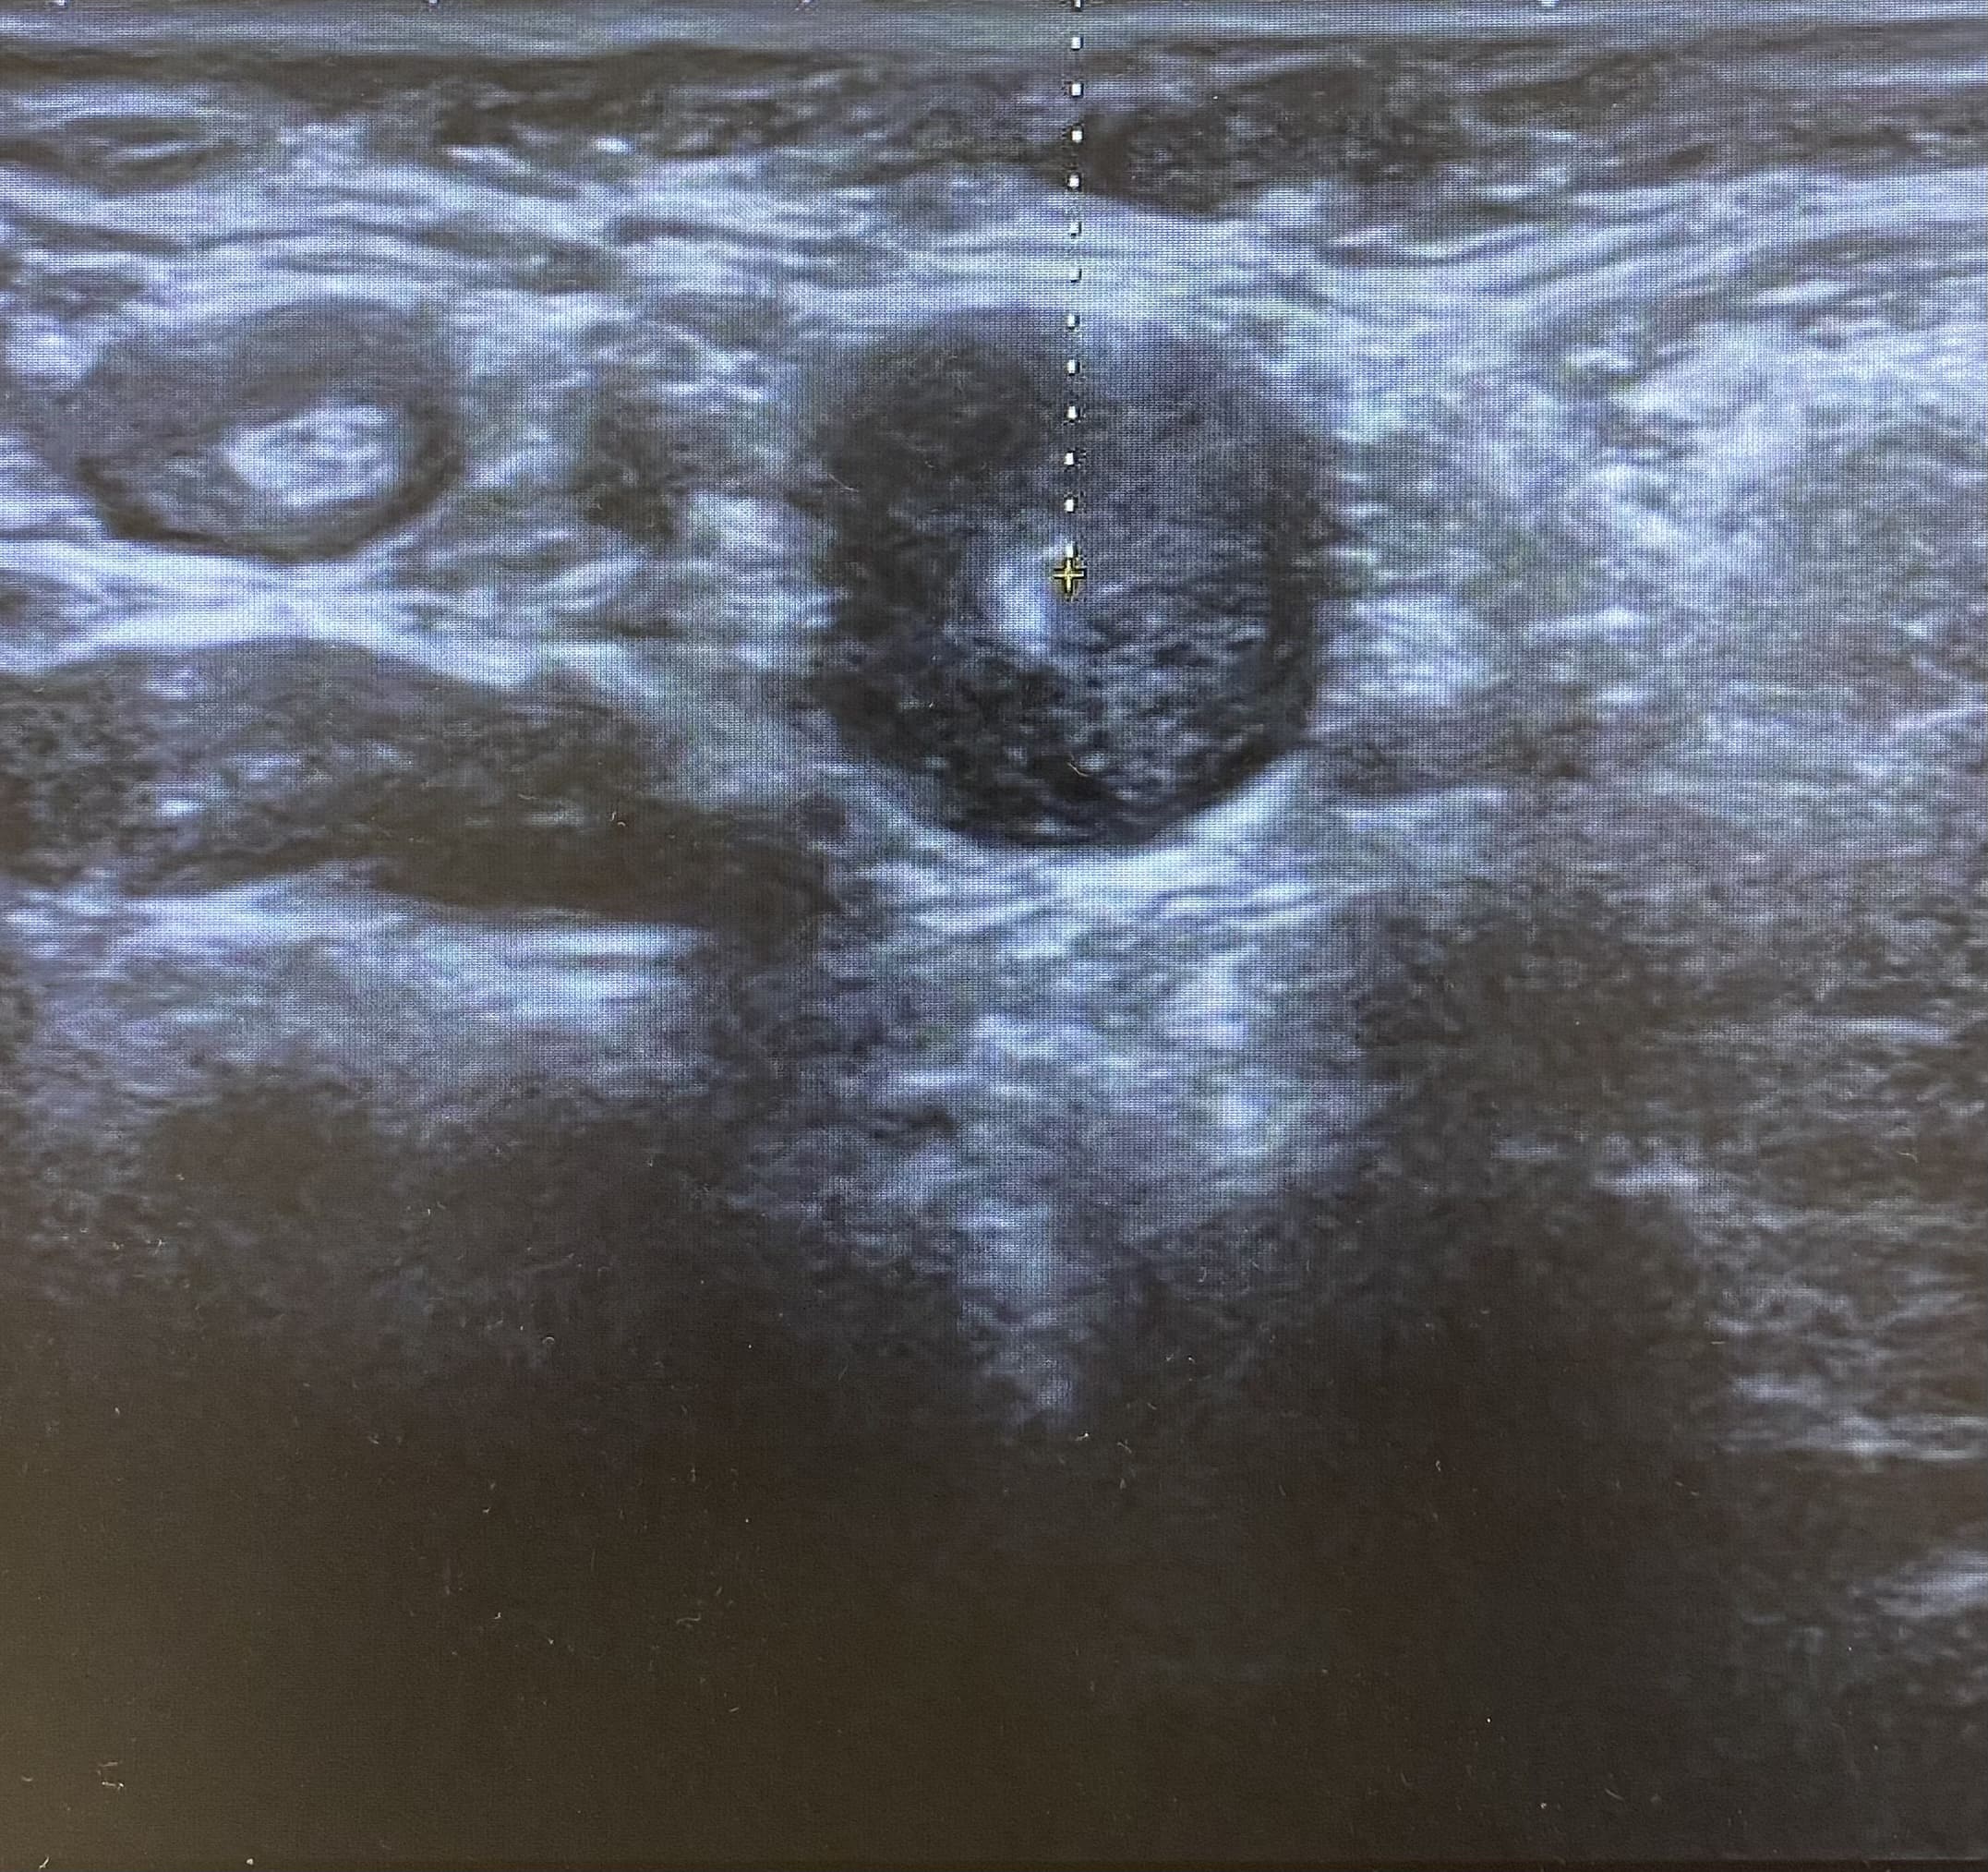

Ecografía: Valoración de adenopatías para acercamiento diagnóstico (típicas/atípicas).

Hallazgos ecográficos

Adenopatías patológicas, algunas redondeadas, con eje anteroposterior > 1 cm, parénquima homogéneo, cortical engrosada aunque con hilio respetado.

Ecografía mamas: quistes y nódulos hipoecogénicos bilaterales.

Ecografía axilar: múltiples adenopatías con eje corto > 2 cm y cortical engrosada.

Se solicita ecografía a radiólogo, coincidiendo en manifestar la existencia de adenopatías de características atípicas. Derivación a medicina interna y cirugía general.